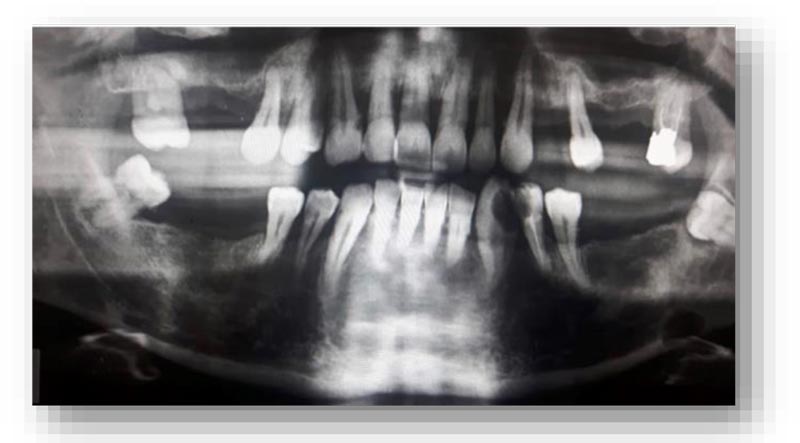

Vincenzo Ronsivalle, Federica Casella, Grazia Fichera, Orazio Bennici, Cristina Conforte and Antonino Lo Giudice